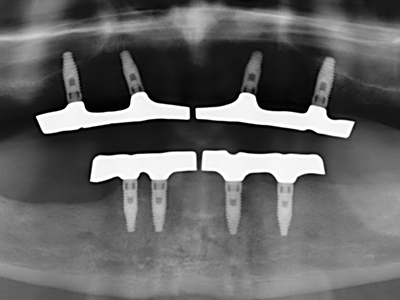

Sollen chirurgische Eingriffe mit unmittelbarer Knochenbeziehung an empfindlichen Strukturen wie Blutgefäßen oder Nerven erfolgen, so bergen rotierende Instrumente ein erhebliches Potential an iatrogener Schädigung. Gerade bei Nervdarstellungen nach iatrogener Schädigung, oder aber im Zuge einer Nervlateralisation für resektive und rekonstruktive Eingriffe oder Implantatinsertionen können piezoelektronische Geräte hilfreich sein Knochendeckel zu präparieren und nervnahe Hartgewebsanteile zu entfernen (Abb. 17-20). Ein leichter Kontakt des Nervstrangs zur Piezospitze bleibt dabei in der Regel folgenlos – allerdings kann eine unvorsichtige Vorgehensweise mit sägeartigen Bewegungen bzw. Ansätzen bei noch vorhandener knöcherner Unterlage durchaus temporäre oder aber auch permanente Nervschädigungen verursachen. Das Risiko einer solchen Schädigung wird jedoch als wesentliche geringer eingeschätzt als unter Anwendung von Säge- oder Fräsinstrumenten (Pereira, Gealh et al. 2014).

Wie sich in der Vergangenheit gezeigt hat stellt prinzipiell jeder knochenchirurgische Eingriff eine mögliche Indikation für die Piezochirurgie dar. So lässt sich die Präparation des mobilen Segmentes bei der Distraktionsosteogenese (Abb. 23-25) und der Sandwichosteotomie mit speziellen Ansätzen bewerkstelligen, ohne die für den Erfolg beider Techniken essenzielle Blutversorgung des krestalen Anteils zu gefährden (Gonzalez-Garcia, Diniz-Freitas et al. 2008).